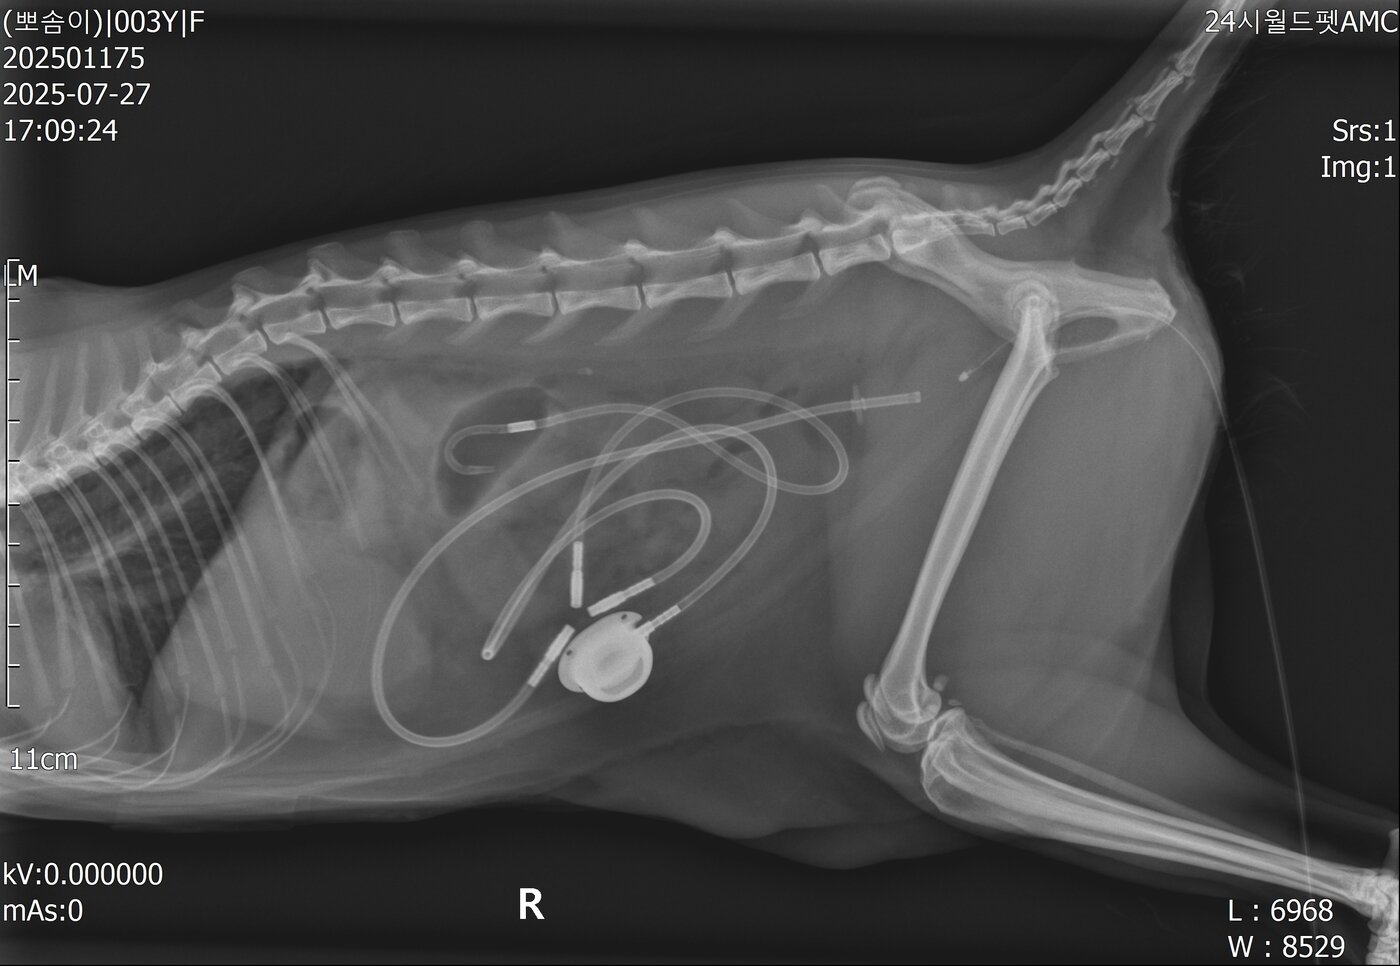

본문 이미지 - 인공 요관을 장착한 모습(월드펫동물메디컬센터 제공) ⓒ 뉴스1

인공 요관을 장착한 모습(월드펫동물메디컬센터 제공) ⓒ 뉴스1